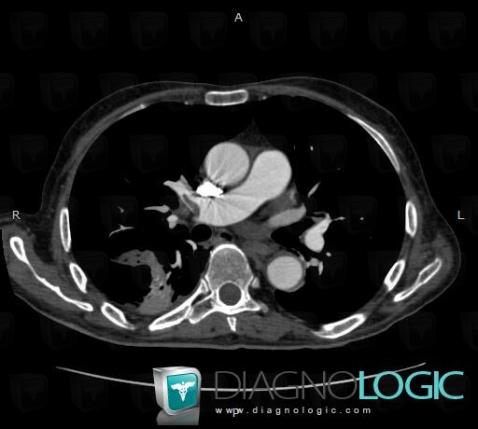

Pulmonary thromboembolism, Pulmonary artery, CT

Here is the specific information in the key image above:

- Diagnosis Pulmonary thromboembolism, Location(s) Pulmonary artery, with gamuts thoracic vascular disease